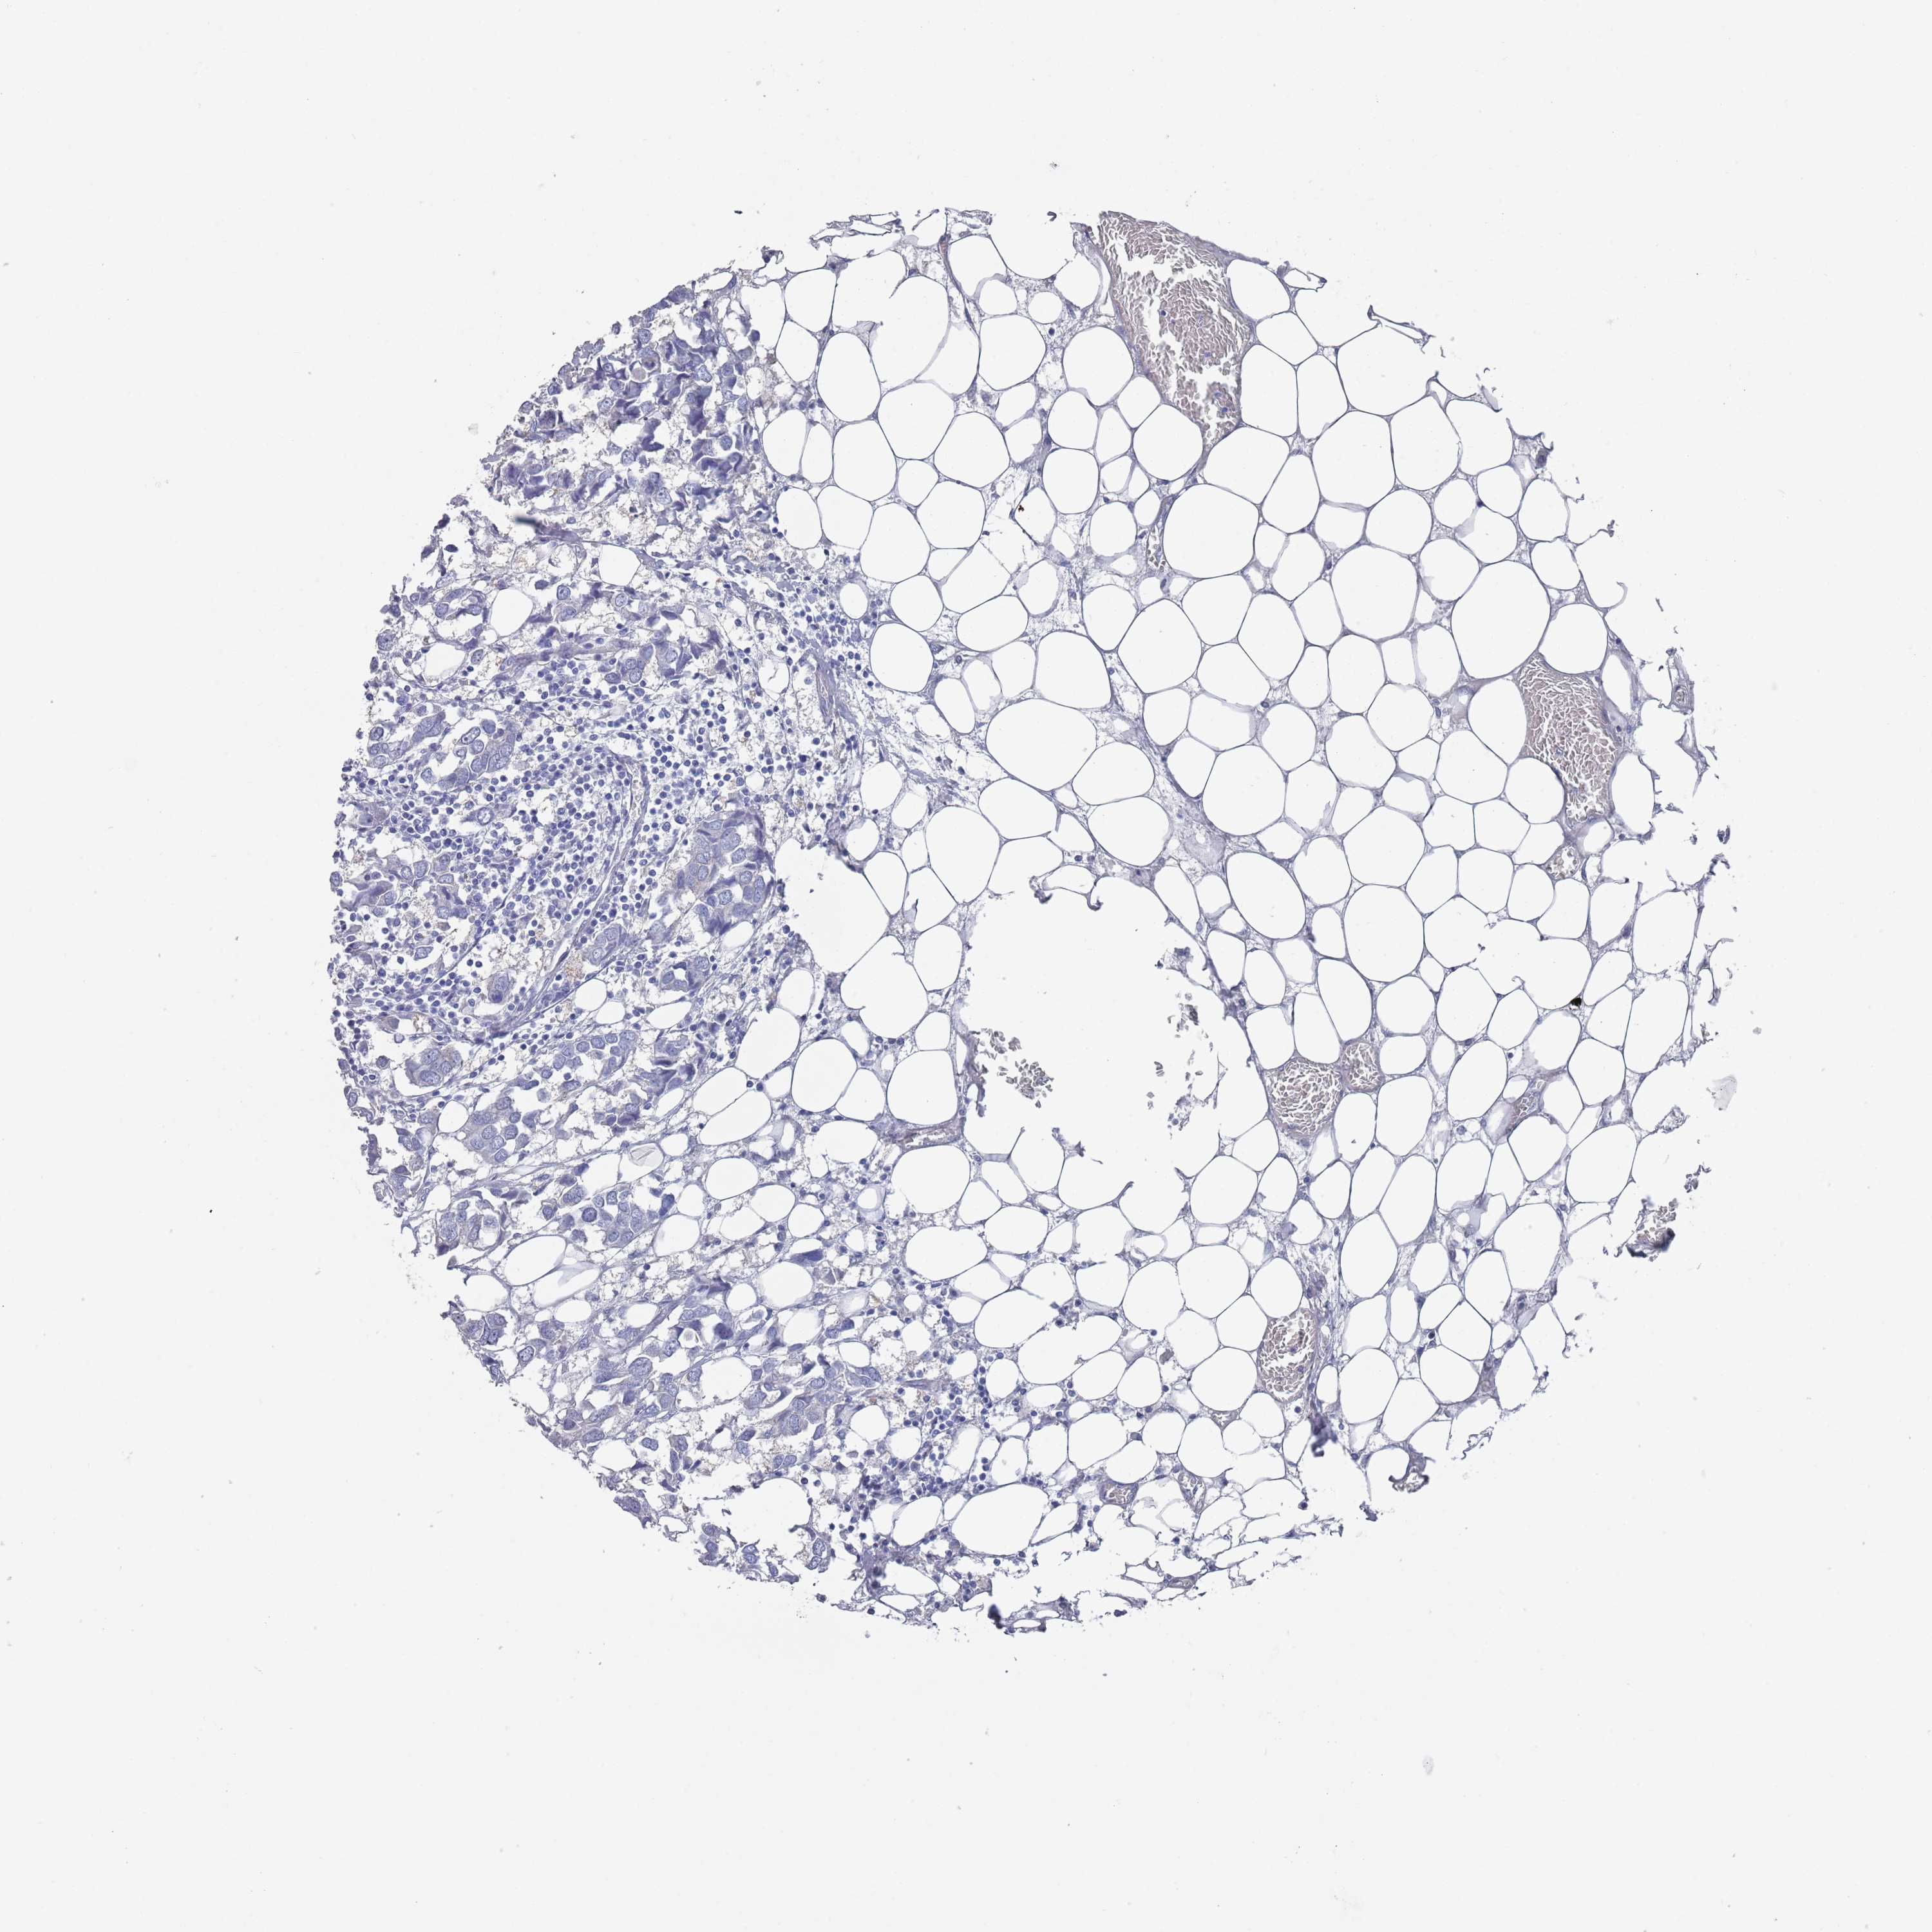

CANCER BREAST CANCER Show tissue menu

BRCA TCGA BRCA VALIDATION PROTEIN EXPRESSION

ANTIBODIES

AND

VALIDATION